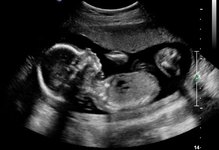

Gebelik, bir kadının vücudunda bir fetüsün geliştiği karmaşık bir süreçtir ve genellikle 40 hafta sürer. Bu süreç, son adet döneminin ilk gününden itibaren hesaplanır ve üç trimester olarak adlandırılan üç ana döneme ayrılır. Her trimester, farklı gelişimsel aşamaları ve fiziksel değişiklikleri içerir. Bu makalede, gebeliğin her haftasını detaylı bir şekilde inceleyeceğiz.

Birinci trimester, gebeliğin ilk üç aylık dönemidir. Bu dönemde, fetüsün temel organları ve sistemleri gelişmeye başlar. Anne adayında ise hormon seviyeleri değişir ve çeşitli fiziksel belirtiler ortaya çıkabilir.

• 12. Hafta: İlk trimester sona erer. Fetüsün tüm organları gelişmiştir ve anne adayının belirtileri genellikle azalır.